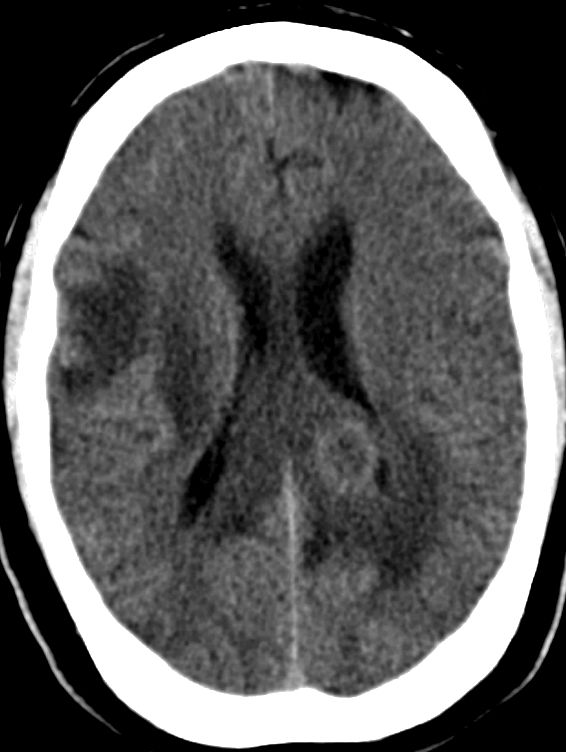

Glioblastom als Rezidiv eines Astrozytoms |

36-jähriger Mann, der vor 7 Jahres ein rechts-frontales Astrozytom Grad II mit Übergang in ein anaplastisches Astrozytom III hatte.![]() |

Jetzt Krampfanfall. Das MRT zeigt ein großes frontales Schmetterlingsgliom.![]() | |||

Die MRT-Kontrolle mit KM vor einem Jahr zeigt eine unauffällige Resektionshöhle.![]() |